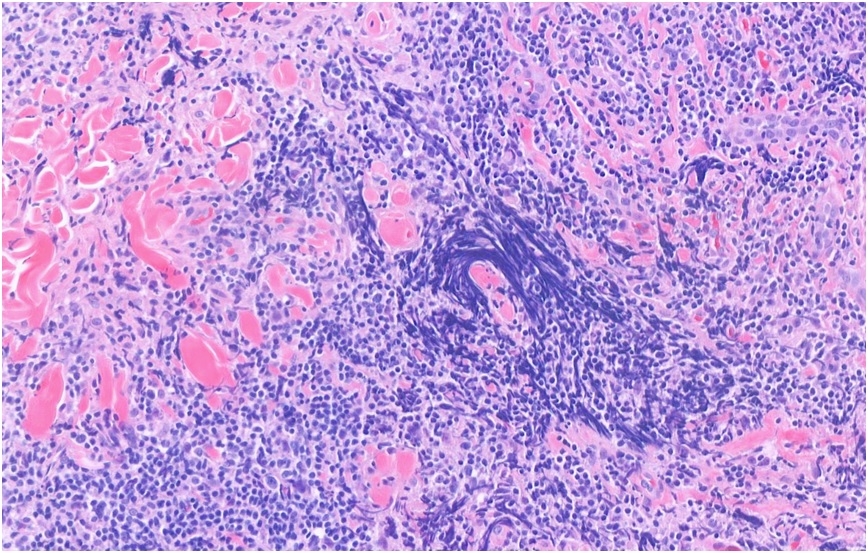

45 Year old male with forehead biopsy Itchy, raised plaque on on frontal hairline (no rash elsewhere). Red patches ?Seborrhoeic dermatitis (raised, erythematous)